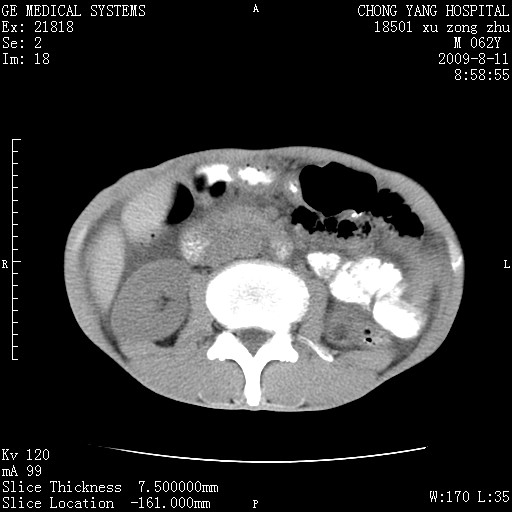

以下是引用杀毒软件在2009-8-11 16:35:00的发言:[br]肝内胆管扩张局限于左叶,胆管内有结石伴肝外胆管结石,胆管壁增厚呈弥漫性并发腹腔积液,胰腺边界模糊。[br][br]考虑---胆总管及肝内胆管结石继发胆管炎及胰腺炎,左肾下极囊肿,腹水。

以下是引用zjzjr在2009-8-11 17:35:00的发言:[br]肝内胆管扩张局限于左叶,胆管内有结石伴肝外胆管结石,胆管壁增厚呈弥漫性并发腹腔积液。[br][br]考虑---胆总管及肝内胆管结石继发胆管炎,左肾下极囊肿,腹水。